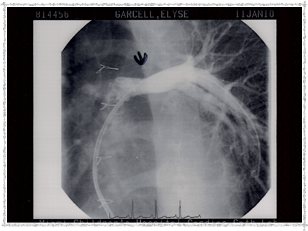

Cardiac Catheterizations

As Elyse grew, her heart needed continued monitoring. She underwent two cardiac catheterization procedures — one in 2003 and one in 2010.

First Catheterization — Dr. Evan Zahn

In 2003, Elyse underwent a catheterization procedure at Miami Children's Hospital, performed by Dr. Evan Zahn. Below are some pictures that Dr. Zahn provided. She left the hospital the same day — remarkable!

Catheterization 2003 - Before

Before the procedure